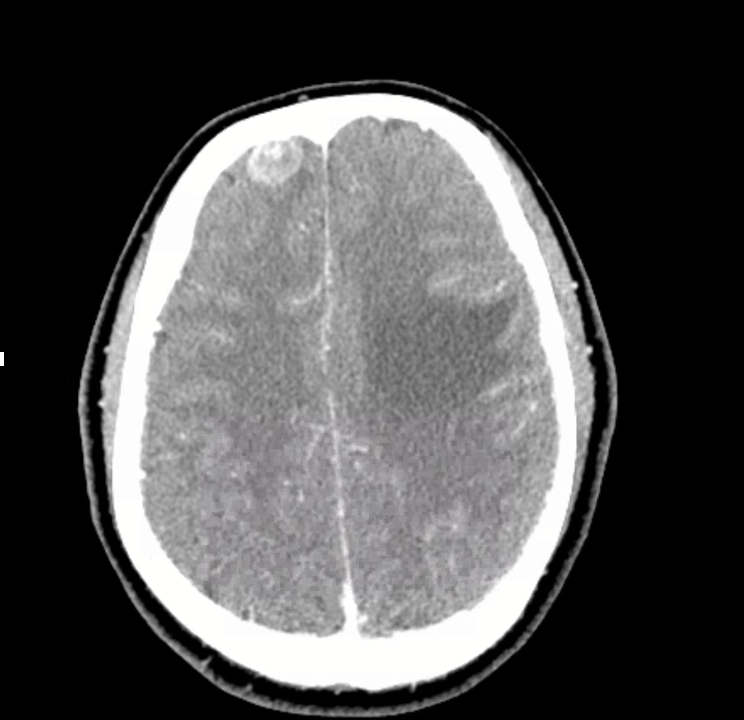

3) Neuro findings—ring-enhancing lesions

• Differential: septic emboli/abscess, nocardia, fungal, TB, parasites, metastases, vasculitis, sarcoid.

• Partner with neuroradiology for pattern nuances; treat seizures but keep searching for the unifying diagnosis.

• Path: TTF-1+, CK7+, napsin A → pulmonary adenocarcinoma with a fusion driver.

• Therapy: Targeted TKI (crizotinib) → dramatic radiographic response of miliary lung disease and CNS lesions.

• Teaching point: even “miliary TB-like” lungs + CNS lesions in a 20-something can be driver-positive lung cancer—don’t let age or pattern blind you.